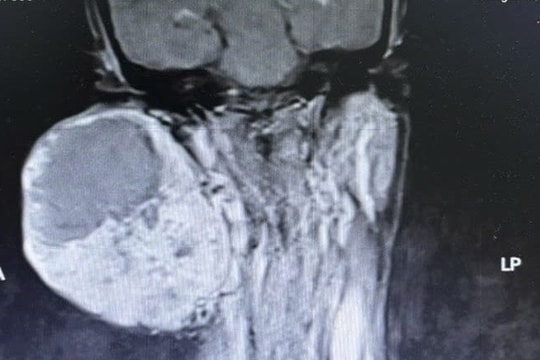

Suýt mất mạng vì mang khối u khổng lồ 14 năm không điều trị

Khối u trên má phải xuất hiện cách đây 14 năm nhưng người phụ nữ không điều trị, gần đây thấy khối u gây đau, đi khám thì biết u bị vỡ, chảy máu trong.